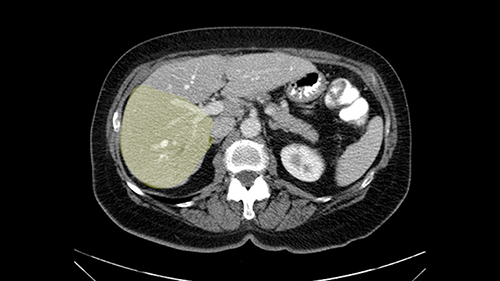

So when doing a major liver resection, obviously we would focus on a few issues. The first is hepatic parenchyma: is there adequate liver, residual liver and orientation and ratio of the right to left lobe here is pretty normal. It looks like its about 60:40 or 70:30, and because its only a right lobe, I probably wouldn’t do any volumes assuming she has normal liver function which I think she does. The only additional feature of interest is that she has received chemotherapy and one can see the effect of chemotherapy on the density of the liver but again, it doesn’t usually cause significant problems with a short course of neoadjuvant chemotherapy, or liver failure.

I am Professor Jacques Belghiti, hepatobiliary surgeon. I practiced at Beaujon Hospital at Paris Diderot University Paris 7. I will discuss the case of a 65-year old patient who has hepatic metastases from a colon cancer operated on one year before. Two particular points with this patient: She has had a cholecystectomy at the time of colectomy, and at the discovery of the lesions in which there were 3, all located in the right liver, we noted the existence of biliary dilatation. This biliary tract dilatation could have been a consequence of the cholecystectomy, or due to a particular form of metastasis with biliary infiltration; and my impression is that the second hypothesis should be supported for two reasons. The first reason is that on the initial CT scan, we had a feeling that the biliary tract dilatation was associated with a small tumor/lesion. The second reason is that the dilatation decreased after several courses of chemotherapy. I don’t know how many courses of chemotherapy she had, but in any case, there exists some lesions of the hepatic parenchyma, with steatosis that may have been a consequence of this chemotherapy. After several courses of chemotherapy, we see at least 2 lesions persisting in the posterior sector of the right liver and dilatation of the biliary tracts. There might be another lesion at the junction of Sg 5 and 8. So this patient should now be operated on since we are faced with lesions that persisted after chemotherapy.

It’s been a few years, I would have done a right hepatectomy. I think it is more sensible now, especially taking into account the current Japanese and Asian practices, to do a more limited operation. So my option will be a generous hepatectomy by traditional ways. I would not do laparoscopic, not because I don’t think it’s good but because I usually don’t do laparoscopy. By classical sense, a formal hepatectomy, a thorough evaluation of the liver manually, visually, and with intraoperative ultrasound to locate all the areas, notably any scarred tissue that could be left behind from previous metastases that shrunk under chemotherapy. In 90% of cases, even if the lesions are not visible on CT or MRI, they are detectable as a form of scarring that should be seen by ultrasound, and you have to find them after having evaluated on ultrasound or by palpation. If I don’t find any other lesions, I would revise for a posterior sectorectomy, taking out Sg 6 and 7 in a generous fashion to get the biliary involvement, and a local resection of the Sg5-8 lesion.